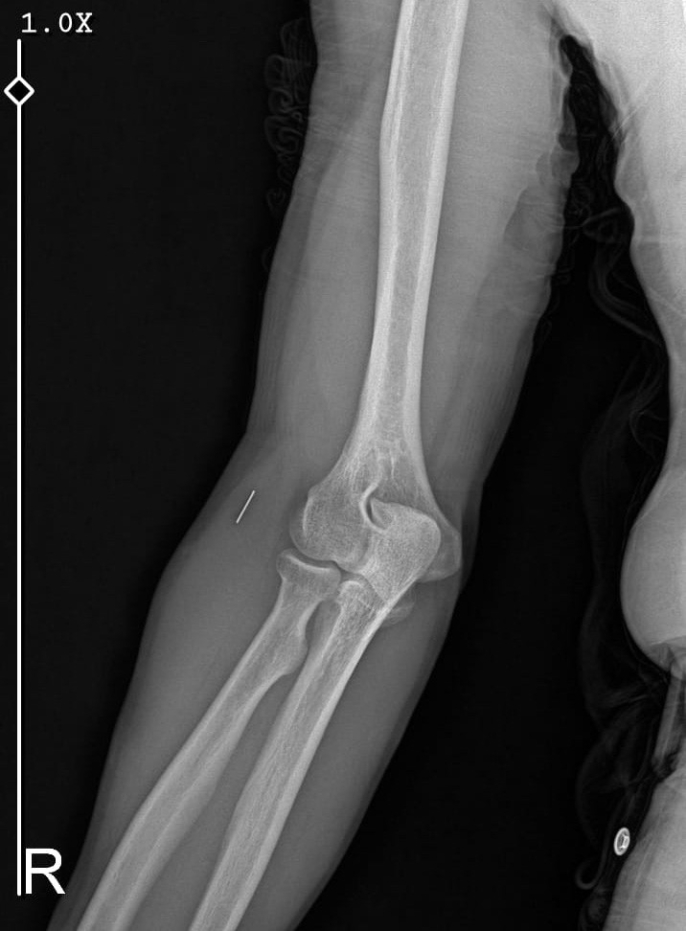

Edinilen bilgilere göre, 7 Haziran 2025'te Kurban Bayramı dolayısıyla bıçak temizlerken sağ el başparmağını kesen Güleryüz (34), ilk olarak bir özel hastanenin acil servisine başvurdu. Ancak hastanede detaylı tetkik yapılmadan yalnızca pansuman yapılarak taburcu edildi. Şikayetleri devam eden Güleryüz, ertesi gün tekrar aynı hastaneye gittiğinde dikiş atıldı. Parmağının hareket etmemesi üzerine 19 Haziran'da başka bir özel hastaneye başvurdu ve burada tendon yaralanması şüphesiyle tedaviye alındı. Yapılan tetkiklerde sinir hasarı ve tendon kopması tespit edilince, 2 Eylül'de ameliyat oldu. Ancak süreç içinde parmağın çürüdüğü belirtilerek ampute edilmesi gerekti.